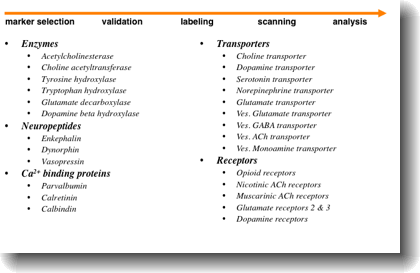

- Digitally acquire and display qualitative and quantitative data of gene expression in the mouse brain for 100 genes in 100 brain regions.

- Characterize the location of neurotransmitter systems and their components in the baseline mouse strain (C57)

- Identify and quantify differences or changes in other mouse strains and under abnormal conditions